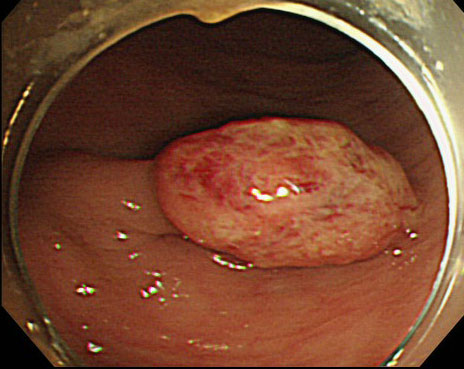

大腸ポリープと大腸がん

大腸内視鏡検査を行った結果、「大腸がん」はないけれど「大腸ポリープ」があったという方が多くいます。実際に大腸ポリープは便潜血陽性で内視鏡検査を行った方の4人に1人程度で見つかるとされています。大腸ポリープは大腸がんの原因となるものです。正常な細胞が増殖するときに遺伝子のコピーミスが起きるとポリープが発生し、そこからさらにコピーミスが発生すると癌ができるといわれています。

このようなポリープの中から大腸がんができてくる